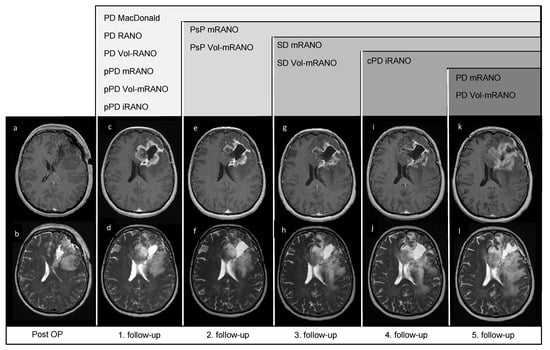

3.6. Pseudoprogression